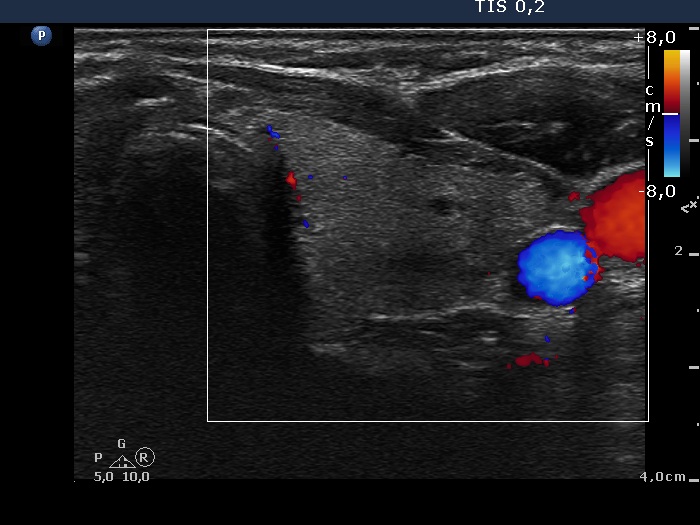

Subacute granulomatous thyroiditis - case 1777 (ultrasonographic picture 9)

Right lobe, longitudinal scan

Left lobe, transverse view, color Doppler mode. The lobe is avascular.